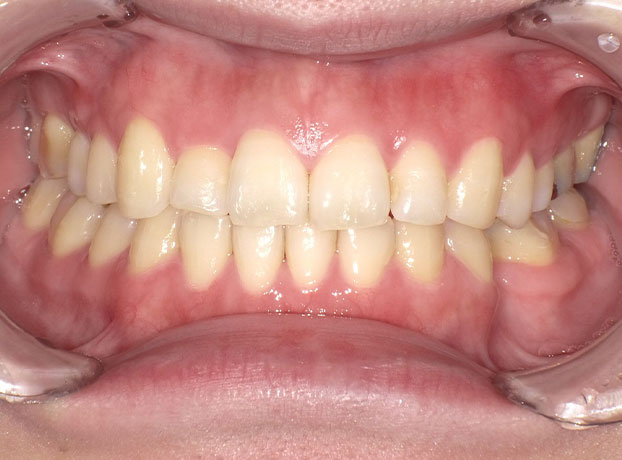

◆ワイヤー矯正(30代女性)

(主訴)歯並びを良くしたい。

右上前歯以外にも奥歯の噛み合わせも改善した方が良かったため、歯の表にワイヤーを装着する、オーソドックスな方法にて矯正。

審美面も機能回復の面でも矯正治療により改善する事が出来た。